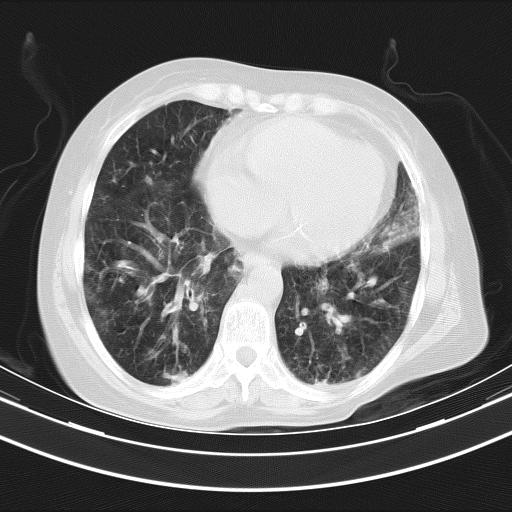

老年女性,嗜睡3天,意识模糊。轻咳,无发热。

双肺多发淡片影,毛玻璃影,,支持支气管肺炎,,建议血气找原因,,嗜睡是否肺性脑病?有没有慢支病史?

1)两肺感染性病变;建议抗炎治疗后复查。2)纵隔淋巴结肿大。3)左侧胸腔积液。